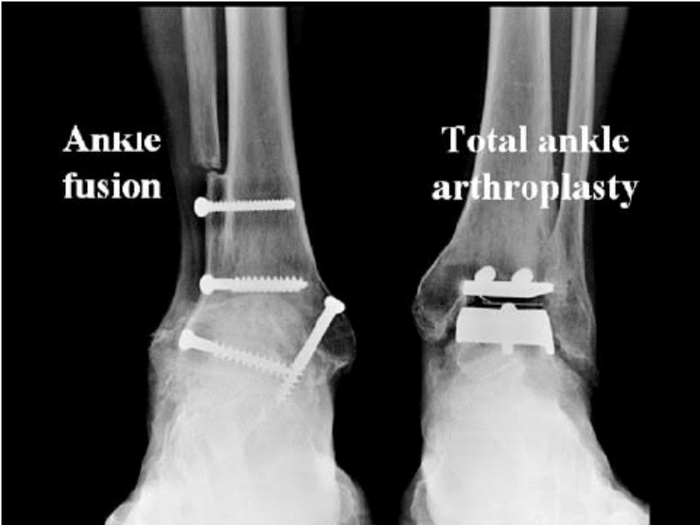

При терминальной стадии артроза голеностопного сустава (когда сустав тотально разрушен), есть два основных варианта хирургического лечения:

эндопротезирование (Эп, использую такие сокращения для простоты понимания) — ставят искусственный сустав, чтобы сохранить движение.

атродез (Ар) — сустав “выключают”: сращивают кости, движения в голеностопе больше нет, зато обычно уходит боль. Сразу обговорю: человек инвалидом не становится, он может ходить и даже заниматься спортом.

Слева артродезирование (то есть голеностопного сустава больше нет), а справа эндопротезирование (его заменили на искусственный).